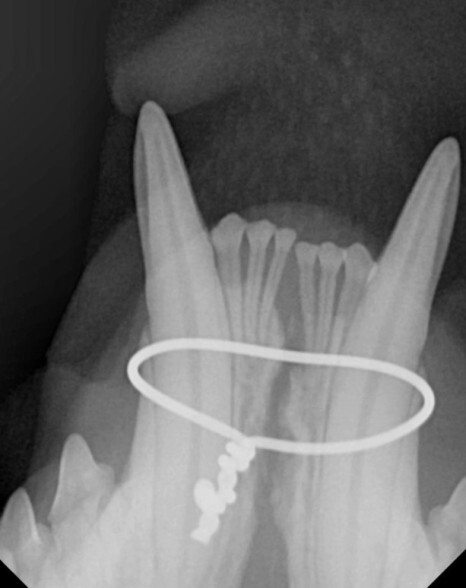

아래턱뼈를 다시 정상 위치로 이동시키기 위한

교정 치료도 함께 진행되었습니다.

다행스럽게 턱관절의 탈구는 없는 것으로 확인되어

교정된 방향으로는 입을 닫는 것이 가능해 보였습니다.

부러진 송곳니는 교정장치를 제거하면서 근관치료를

하고 1차 수술을 종료하였습니다.

며칠 후 교정장치 없이도 제 위치로의 교합을

확인한 후 근관치료를 진행하였습니다.